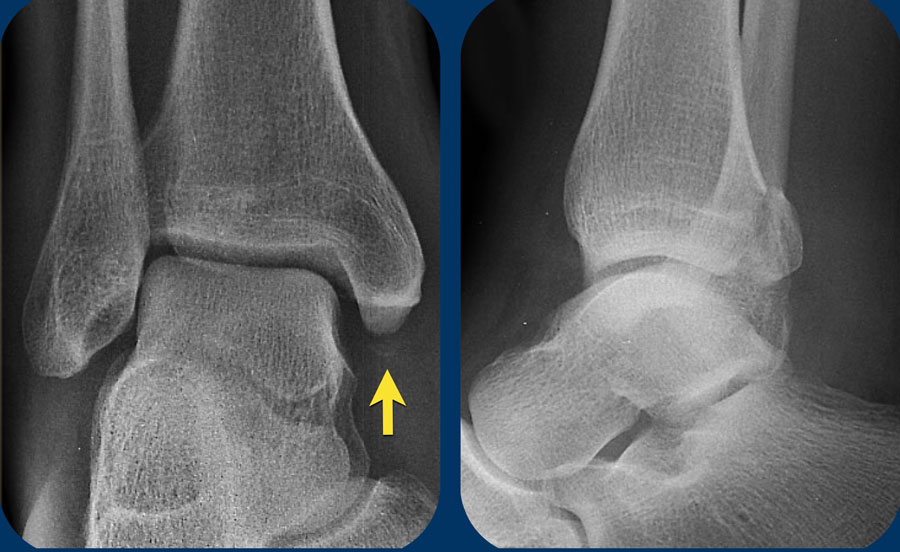

Hình bên trái là một ví dụ khác về gãy xương hai mắt cá không ổn định giai đoạn 2 Weber A.

Hình bên phải cho thấy đường gãy thẳng đứng của mắt cá trong (mũi tên). Đây luôn là giai đoạn 2 và không ổn định. Điều này có nghĩa là giai đoạn 1 đã xảy ra trước đó, vì cơ chế chấn thương luôn tuân theo trình tự nghiêm ngặt: giai đoạn 1 trước, sau đó mới đến giai đoạn 2.

Vòng ổn định bị phá vỡ ở hai vị trí (cuộn ảnh để xem).